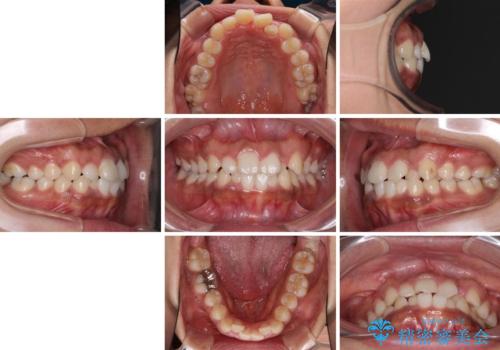

- 上下前歯の叢生を気にして来院された患者様です。

当初はインビザラインにて治療を開始しましたが、自己管理による治療が難しくなり、ワイヤー矯正へ転換して継続しました。